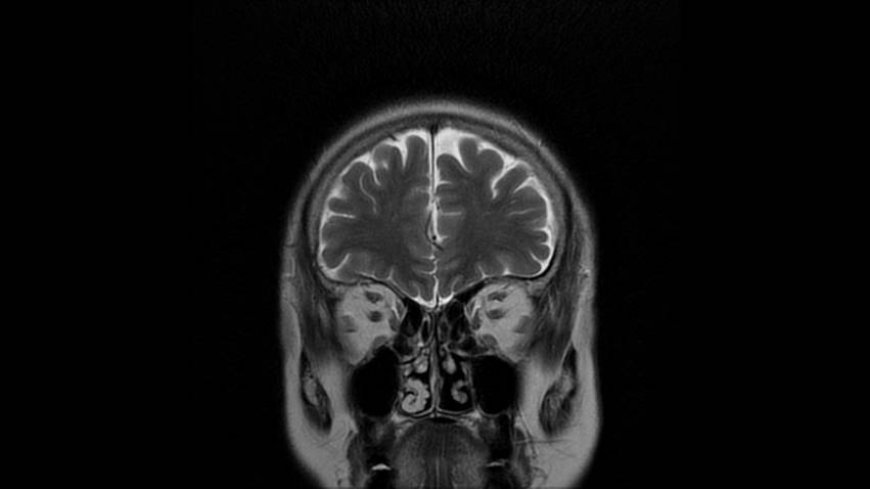

MRI of Brain

Coronal T2